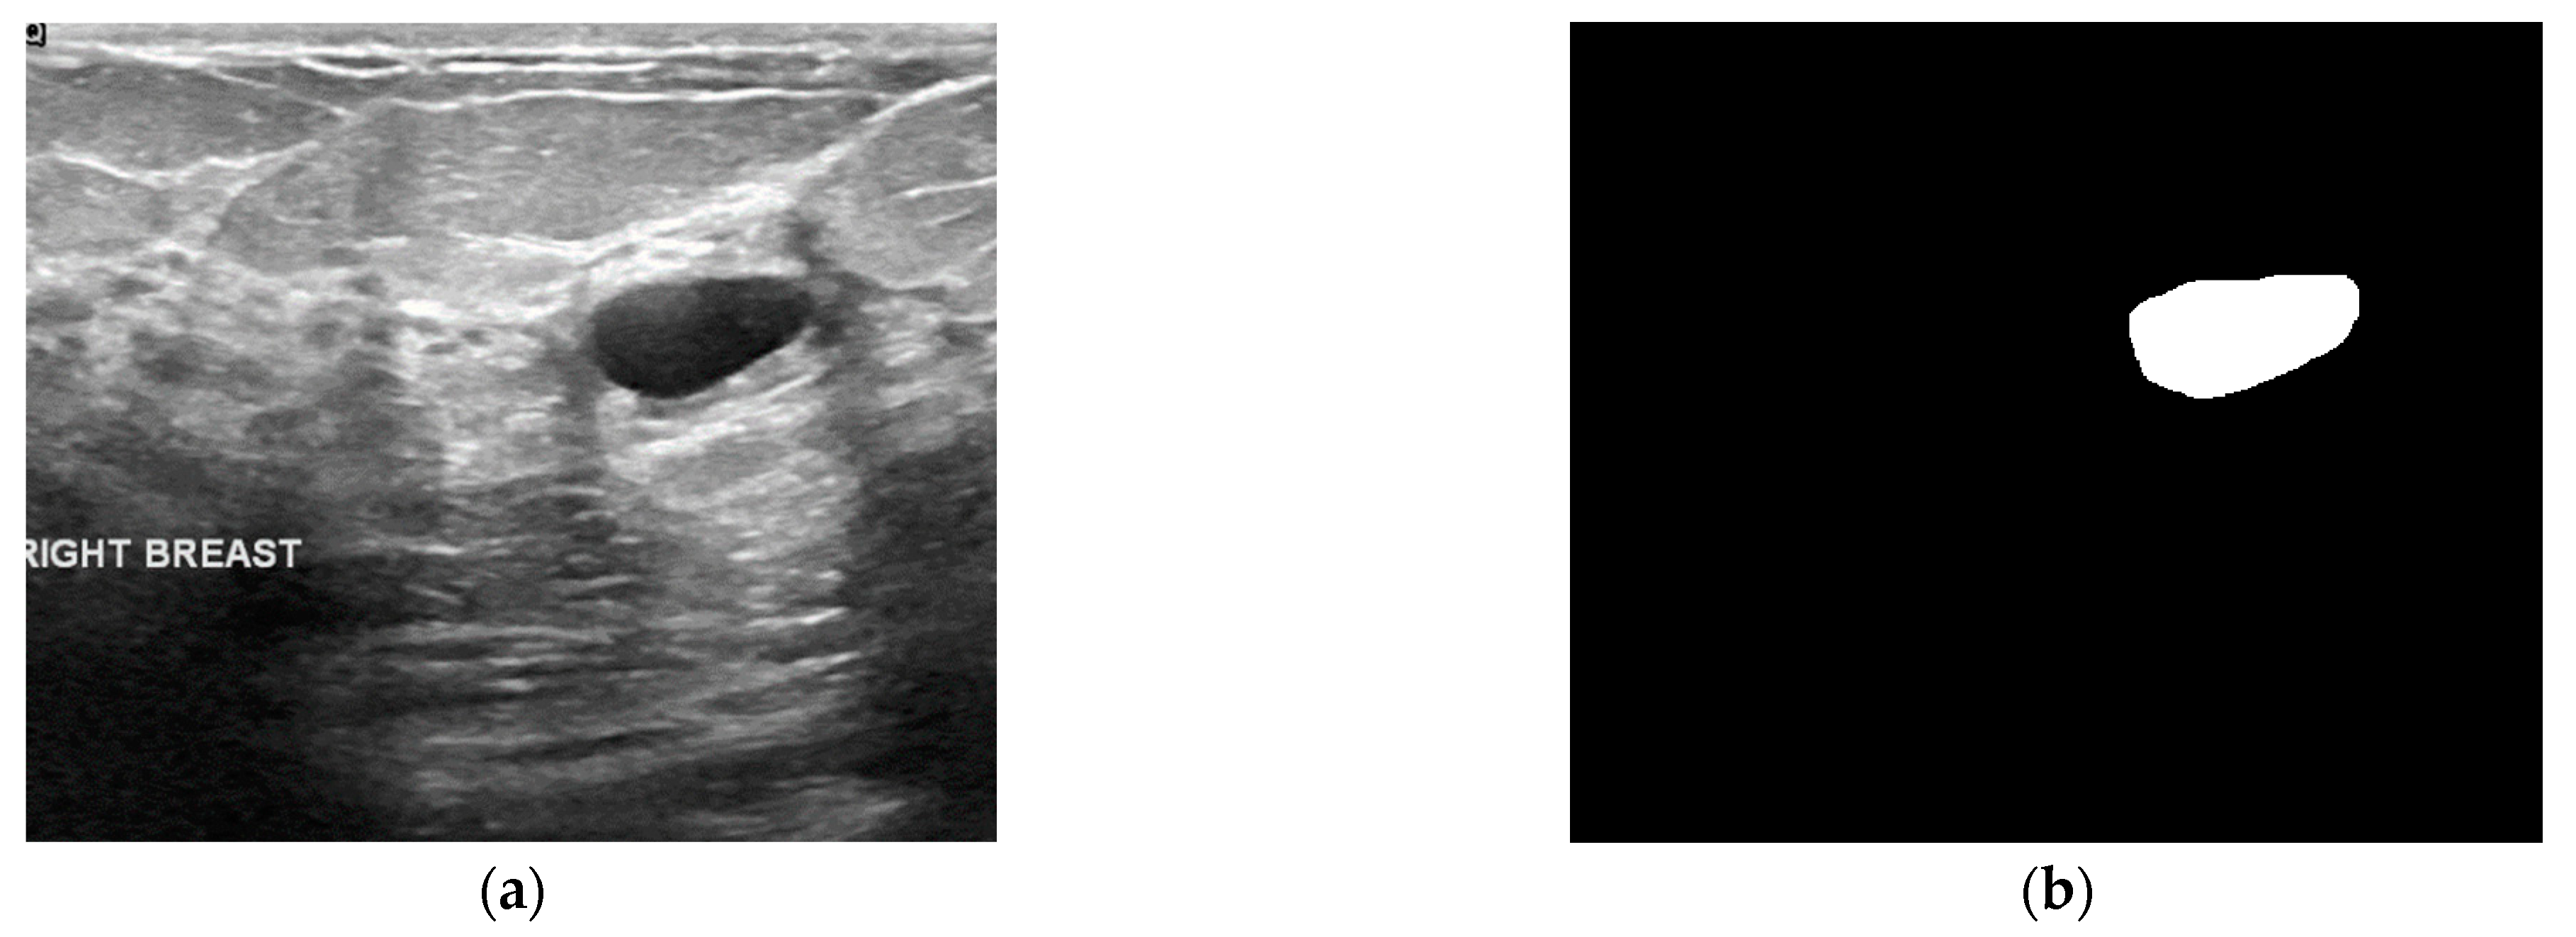

3.1. Dataset